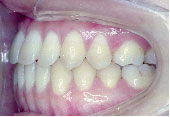

あごのずれもなくなり、バランスのとれた美しい口元になりました。咬み合わせも非常に良くなってご本人は大変満足されています。

治療期間は3年7か月です。

ここまでの費用は、総額約27万円です。

(公的医療保険が適用されています。これ以外に外科手術費用がかかりますが、公的医療保険に加え高額療養費制度の適用になります。)